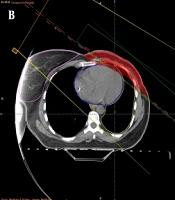

Comparison of 3D-Conformal Planning Using Partially Wide Tangents and Direct Photon/Electron Portals for Breast Radiotherapy with Internal Mammary Nodes Inclusion: A Dosimetric Analysis

Farshid Farhan,

Sepideh Sehat Kashani ,

Farnaz Amouzegar-Hashemi,

Peiman Haddad,

Mohammad Babaei,

Ebrahim Esmati

,et al.19